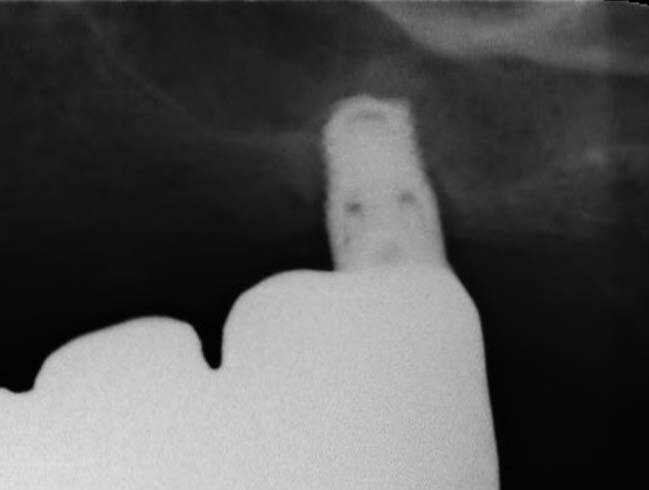

Il paziente di 50 anni in buono stato di salute, necessitava di una riabilitazione di tutta l’arcata superiore sia con impianti nei settori posteriori sia con corone sui denti frontali. Mentre nel sestante superiore destro era presente una quantità d’osso ideale per l’inserimento di impianti di diametro e lunghezza considerati standard, nel sestante sinistro era presente una quantità d’osso insufficiente sia verticalmente che orizzontalmente (Figg. 1-4). A causa dei timori del paziente sono stati esclusi interventi invasivi per incrementare i volumi ossei e si è deciso di inserire in posizione 24 un impianto BTI 3.0 3,3 x 10 mm e in posizione 26 un impianto BTI standard 3,7 x 5,5 mm con un minirialzo contestuale del seno mascellare.

Ad un anno di distanza dalla consegna è stato eseguito un controllo radiografico (Fig. 10). Il dettaglio ingrandito della radiografia periapicale evidenziava una maturazione dell’osso attorno all’apice dell’impianto all’interno del seno mascellare. Clinicamente il tessuto gengivale appariva sano e senza alterazioni.